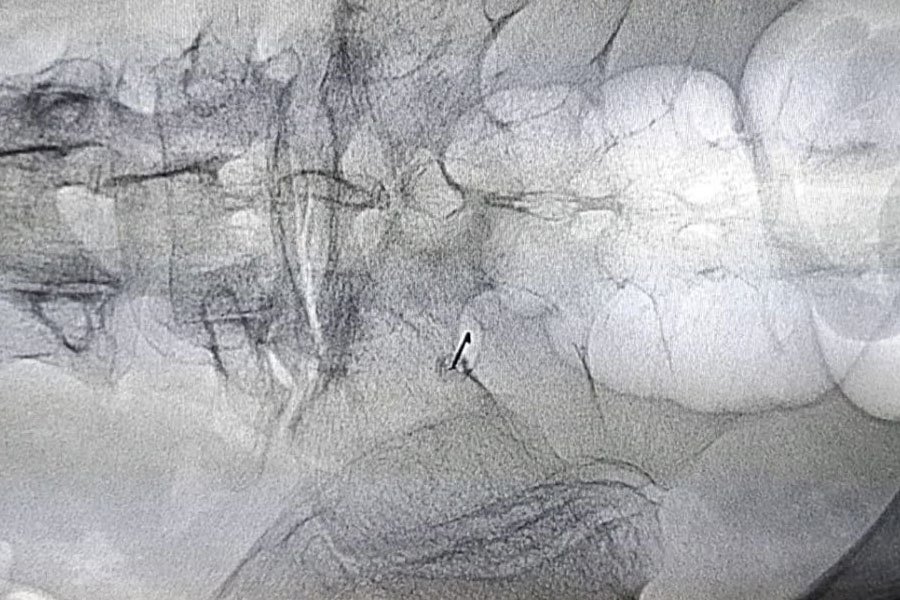

L’infiltrazione epidurale o peridurale è una procedura che prevede l’iniezione di un farmaco antidolorifico nei pressi delle radici nervose nella colonna vertebrale. Gran parte dei pazienti che si sottopongono al trattamento peridurale soffre di dolore neuropatico, come nel caso del dolore causato da ernia del disco.

La terapia epidurale è spesso il primo trattamento interventistico nelle radicolopatie da ernia del disco; infatti la terapia peridurale antalgica è considerata il gold standard nel trattamento conservativo della lombosciatalgia. Il trattamento peridurale ha lo scopo di iniettare sulla radice nervosa infiammata da cui origina il dolore una miscela di steroide ed anestetico, che hanno rispettivamente attività antiinfiammatoria ed analgesica.